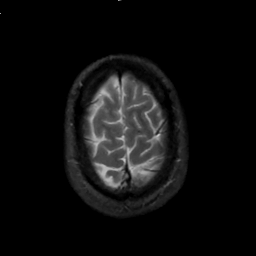

MR Study #1, February 10, 1991 -- Slice #44

[Home][Help][Clinical][Tour 1][Tour 2] Slice 44